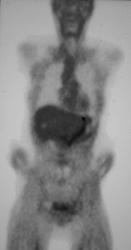

Gastric Adenocarcinoma With Celiac Nodes and Liver Metastases